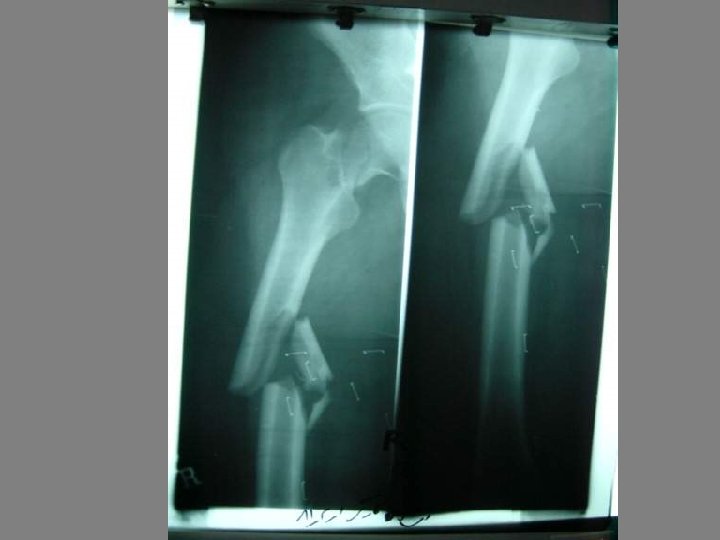

EMERGENCY A AIR WAY BREATHING BLEEDING B CIRCULATION C

thomas